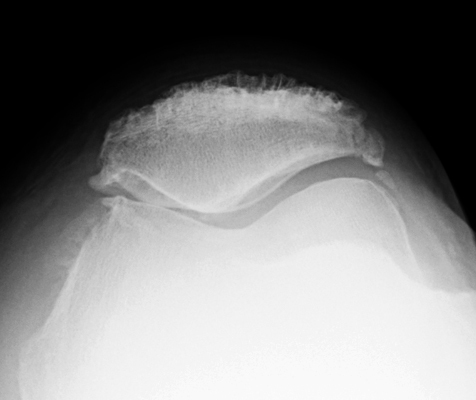

Enthesopathy of the patella at the attachment of the quadriceps tendon on the axial view of the patella (sunrise view) resemble teeth.

Sunrise view - Click on the image for a larger versionALateral Knee - Click on the image for a larger versionB